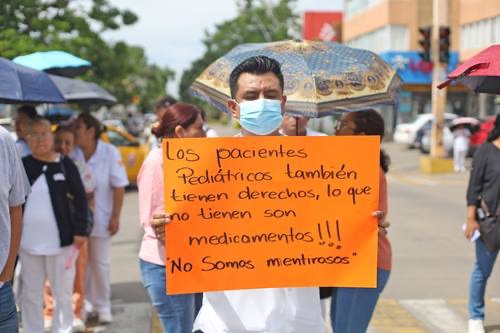

Trabajadores del Hospital Civil advierten riesgo de paro: denuncian desabasto y abandono bajo el IMSS-Bienestar

Personal sindicalizado del Hospital General «Dr. Aurelio Valdivieso» —el principal nosocomio público de Oaxaca— protestó el 25 de junio frente a sus instalaciones para denunciar una crisis que llevan meses documentando sin respuesta: desabasto de medicamentos e insumos, autoclaves descompuestas que imposibilitan la esterilización quirúrgica, elevadores con fallas recurrentes, calderas averiadas y una cocina en […]